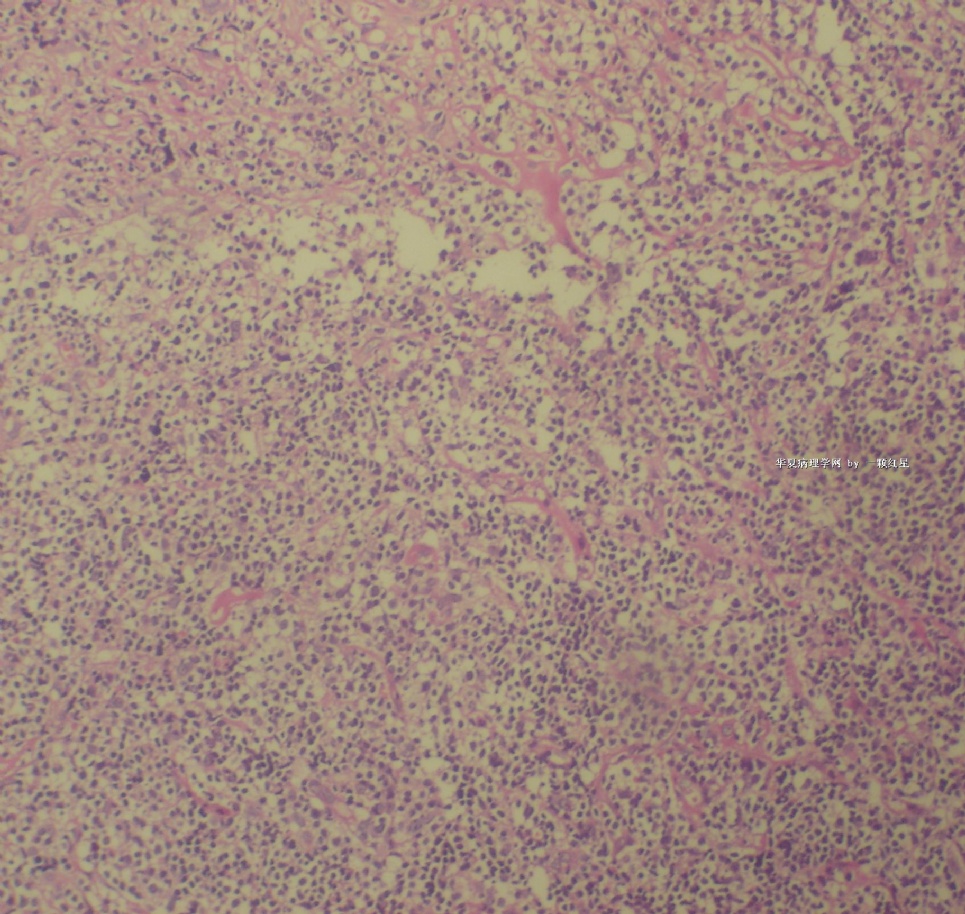

标本名称:  左前臂数个大小不等的皮下肿物。

既往有非何杰金淋巴瘤(滤泡性淋巴瘤)病史22个月。

• 左前臂数个大小不等的皮下肿物     淋巴瘤?图4

图4

病例不错。细胞胞浆透亮,间质血管丰富,图片不是很清晰,似乎有嗜酸粒细胞?

恶性,首先考虑T-NHL。IHC证实。

既往有NHL病史,图片不太清晰,细胞弥漫,胞浆透亮,首先考虑T细胞淋巴瘤。